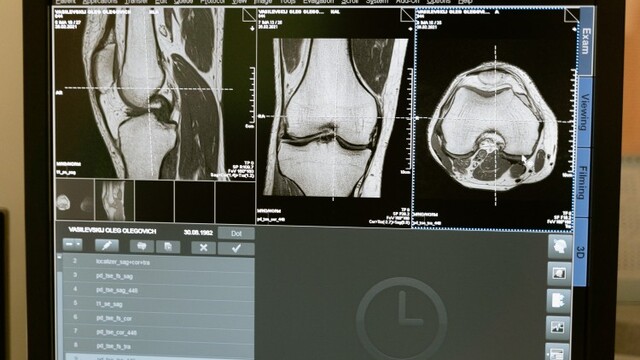

Epidémia zlomenín

Počet zlomenín bedrového kĺbu pribúda každý rok až šesťnásobne. Osteoporóza je nová epidémia, riešenie však môže byť jednoduché a lacné - bezpečné opaľovanie. V štúdiách so staršou populáciou, ktorá utrpela zlomeninu bedrového kĺbu, sa preukázalo, že až 40% z nich malo nedostatok vitamínu D.